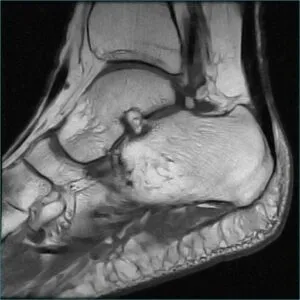

MRI

GE社製のSIGNA Creator 1.5T(テスラ)を導入しています。強力磁石と電波を使って体内の状態を鮮明に見ることができます。膝関節疾患を始めとする他の関節の疾患はもちろん、神経、筋肉・腱の異常や、腫瘍病変などの診断に有用です。

MRIで検査した画像